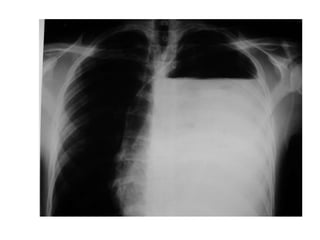

Condensación basal izquierda retrocardíaca

NEUMONIA ATIPICA (legionella)